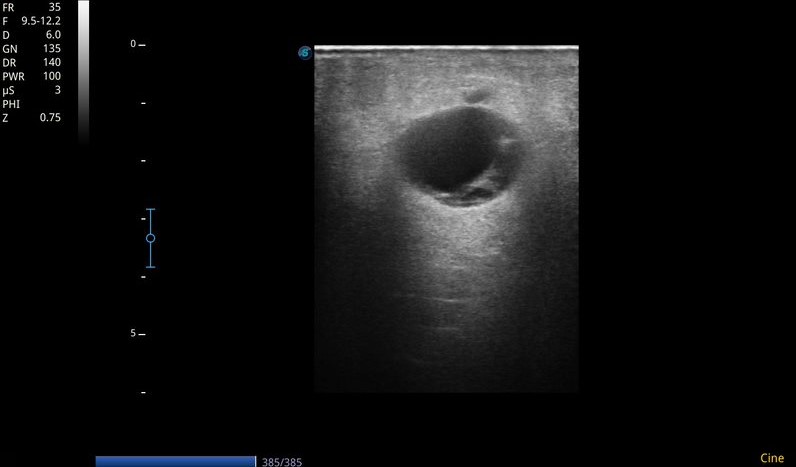

Ecografía MII: Sistema venoso profundo permeable, compresible en todo su recorrido, sin contenido hiperecogénico en su interior. Sistema venoso superficial permeable. Se objetiva a nivel de tejido celular subcutáneo de región interna de tercio superior de muslo izquierdo, colección anecoica, tabicada, no vascularizada, con algunos ecos en su interior, de unos 3-4 cm, con sombra acústica posterior. Importante edema en empedrado en pierna izquierda compatible con celulitis.